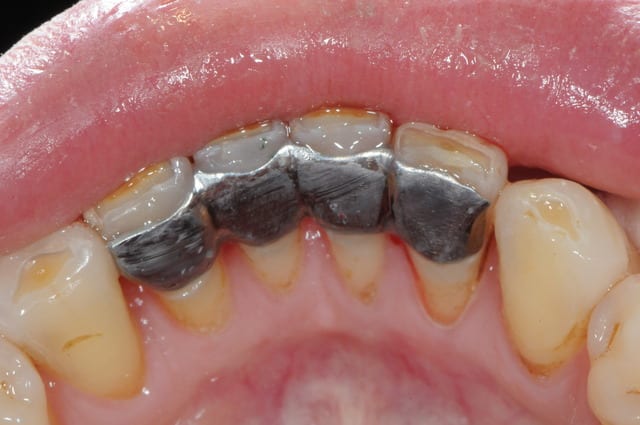

avec la céramique... c'est mieux

scellement fuji